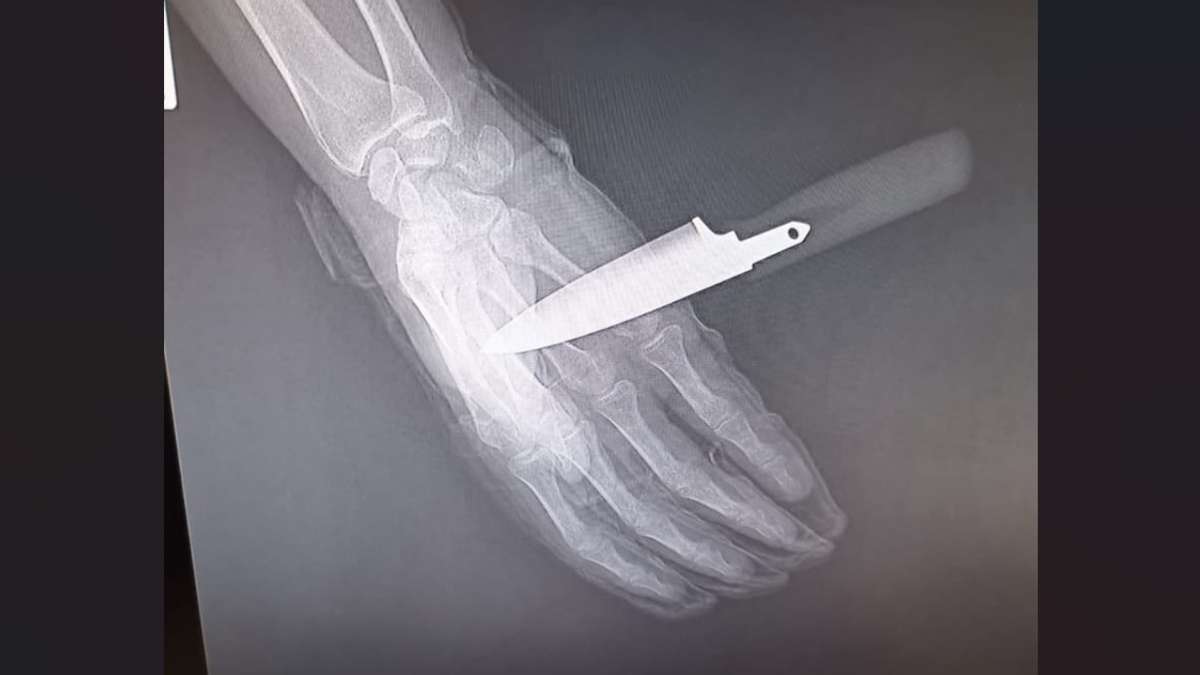

Detenido tras clavar un cuchillo en la mano a un policía nacional en Baza

El agente herido tuvo que engrilletar y trasladar hasta la comisaría a su agresor con el arma blanca incrustada en la mano...